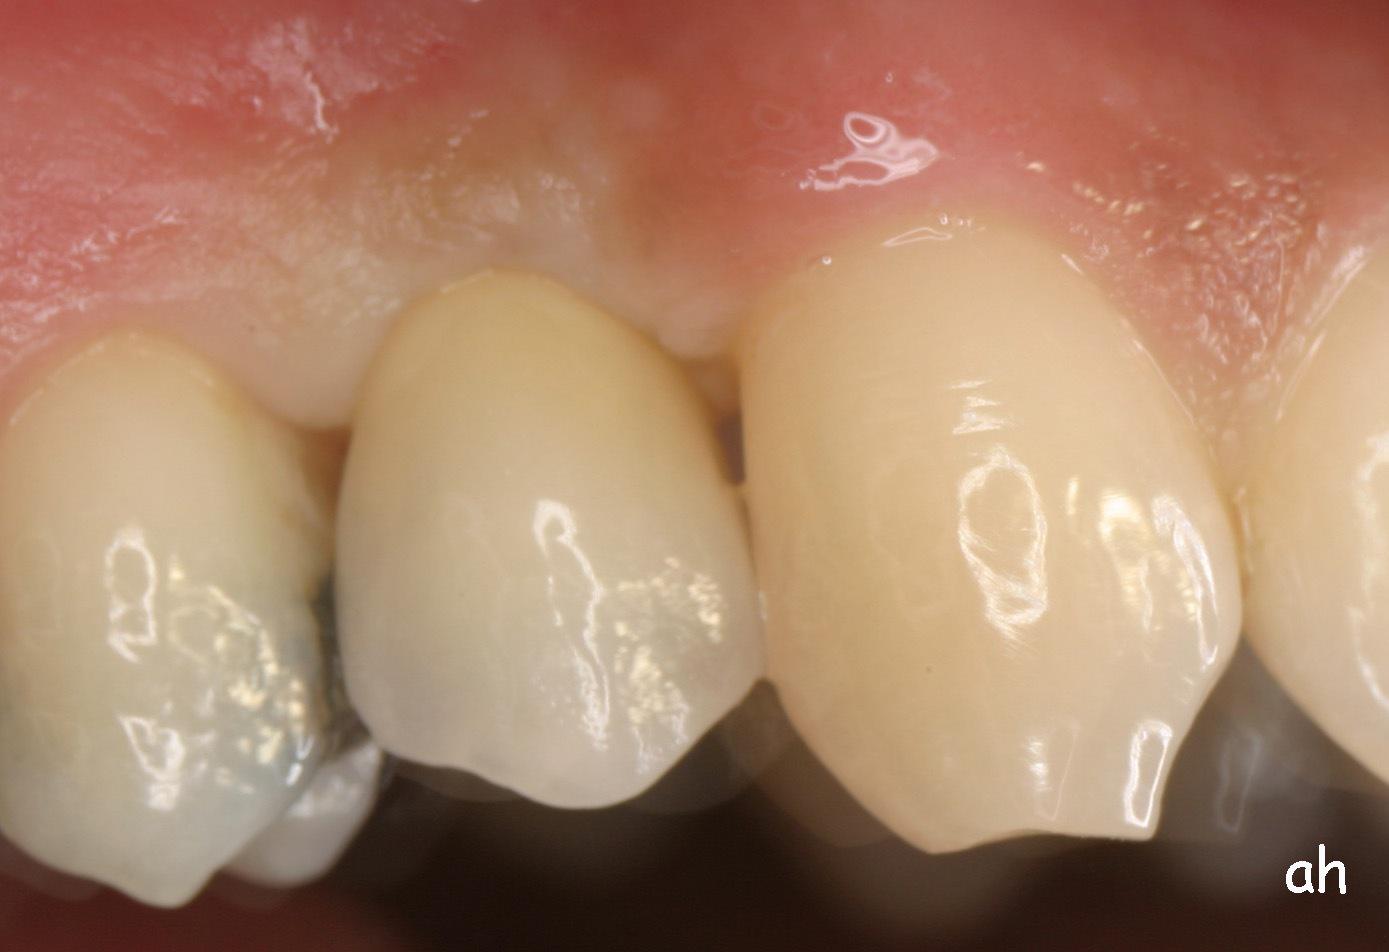

Exemple 1: Ce patient a perdu son incisive centrale gauche lors d'un accident. Un implant a été posé

Exemple 1: L'implant remplace la racine de la dent manquante

Exemple 1: L'implant s'est intégré dans l'os, une empreinte est effectuée. Le laboratoire peut réaliser la couronne en céramique.

Exemple 1: résultat final.